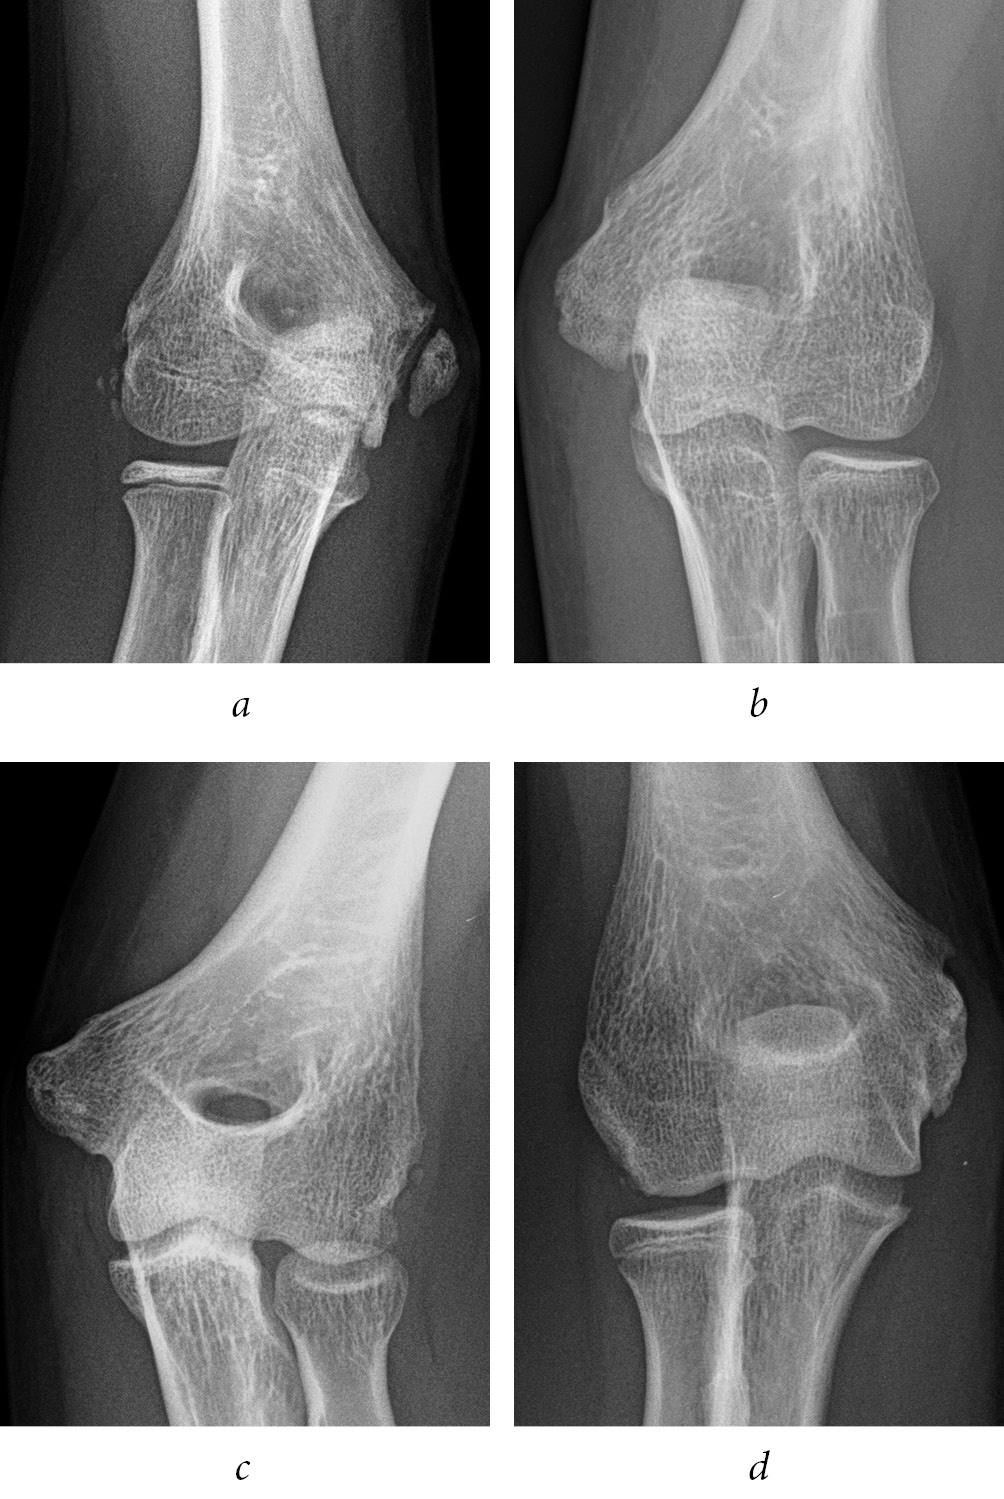

After approval of the study by the local ethics committee, the database of “Salesi” Children’s Hospital was mined for the records of all patients who presented to the Emergency Department (ED) with MEF from 1 January 2014 to 31 December 2017. The MEF were classified by an Orthopaedic surgeon, according with the classification described by Watson-Jones (WJ) [9] and reported by Papavasiliou [10]. The Inclusion criteria were MEF with intra-articular elbow entrapment, isolated (WJ type 3) or in association with elbow dislocation (WJ type 4). There were 13 children, 5 boys and 8 girls, whose mean age was 10.9 years (Range 8–13 years). Six patients reported a MEF with intra-articular elbow entrapment isolated (WJ type 3) and seven patients reported a MEF with intra-articular elbow entrapment after undergoing closed reduction for an associated posterolateral elbow dislocation (WJ type 4) (Fig. 1). Six patients presented with preoperative paresthesia in the ulnar nerve field. Standard anteroposterior and lateral plain films of the injured elbow were obtained at the ED. One patient receive a pre operatively 3D CT scan to confirm intra-articular entrapment (Fig. 2). All of MEF in our cohort were classified by an orthopaedic surgeon. The patients’ parents/guardians gave their informed consent to the use of the children’s medical charts. The mean follow-up was 24.1 months (range 11–44 months). The postoperative clinical evaluation was performed by the evaluation of the passive and the active range of motion (ROM), functional results using the Mayo Elbow Performance Score (MEPS) [11, 12], pain evaluated with the Visual Analogue Scale (VAS) [13]. The radiographic evaluation of fracture healing was performed on standard elbow X-ray after the removal of implants. All the surgical operations were performed by the senior Author (MM). For any patient, at final follow up, the evaluation of the deformity of the MEF after internal fixation was detected by Skak et al classification [14]. The complications were also reviewed (Table 1).

Fig. 1. Patient S. Elbow dislocation with ME intraarticular entrapment: a, b — X-ray of elbow dislocation; c, d — X-ray post-reduction of elbow dislocation with ME intraarticular entrapment